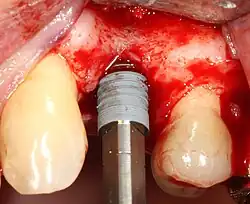

Placing the implant

Most implant systems have five basic steps for placement of each implant:[28]: 214–221

- Drilling at high speed: After reflecting the soft tissue, and using a surgical guide or stent as necessary, pilot holes are placed with precision drills at highly regulated speed to prevent burning or pressure necrosis of the bone.

- Drilling at low speed: The pilot hole is expanded by using progressively wider drills (typically between three and seven successive drilling steps, depending on implant width and length). Care is taken not to damage the osteoblast or bone cells by overheating. A cooling saline or water spray keeps the temperature low.

- Placement of the implant: The implant screw is placed and can be self-tapping;[50]: 100–102 otherwise, the prepared site is tapped with an implant analog. It is then screwed into place with a torque controlled wrench[54] at a precise torque so as not to overload the surrounding bone (overloaded bone can die, a condition called osteonecrosis, which may lead to failure of the implant to fully integrate or bond with the jawbone).